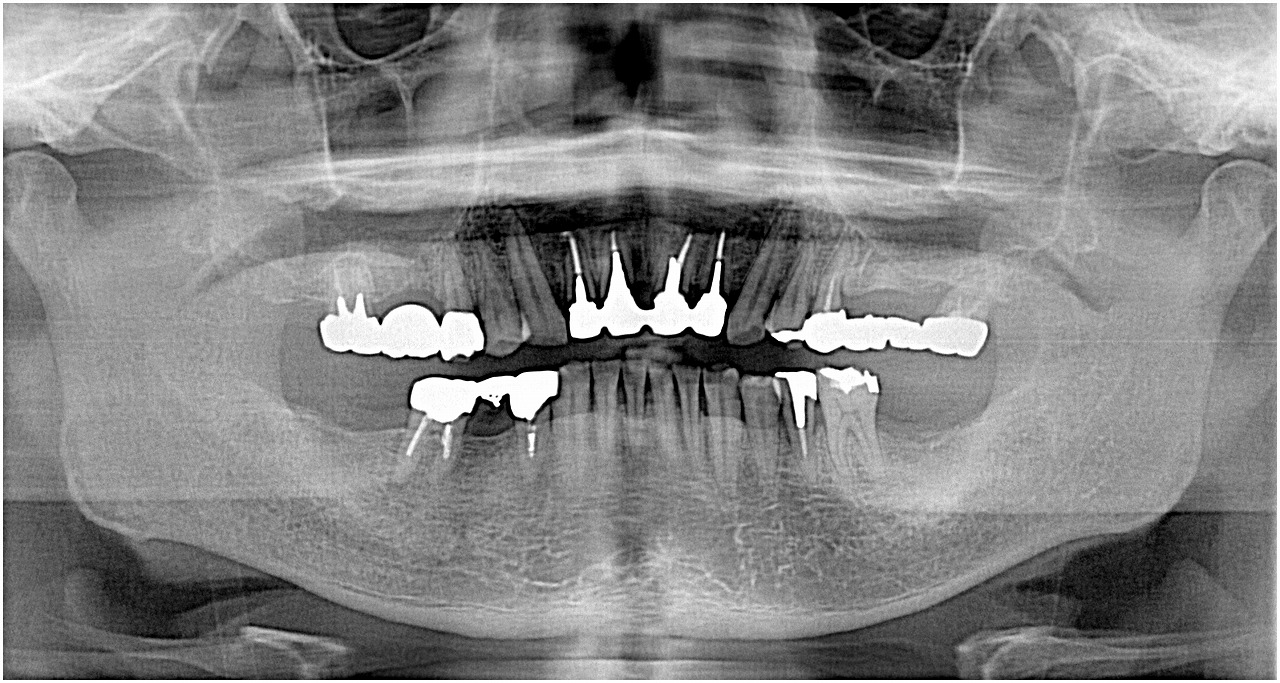

ブログ一覧|広島市安佐南区の歯科医院 ブログ一覧 トップ ブログ一覧 お知らせ スタッフブログ ブログ一覧 2017/12/01 インプラントが厳しいと感じるケースもあります。 ソケットリフトケース。 2017/12/01 インプラントが厳しいと感じるケースもあります。ソケットリフトケース。 埋入位置を口蓋側にもっていくしか固定がえれないケース。 2017/12/01 インプラントが厳しいと感じるケースもあります。ソケットリフトケース。 2017/12/01 インプラントが厳しいと感じるケースもあります。 2017/12/01 術後のレントゲン、CTになります。 2017/12/01 最後臼歯のインプラント埋入。 最後臼歯は難しいです。 2017/12/01 治療計画からCTを基に埋入まで。 2017/12/01 抜歯即時インプラント埋入。 CTデータからひも解くインプラント埋入位置。 埋入深さ。 << 1 2 3 4 5 … 815 816 817 818 819 … 870 871 872 873 874 >> Web診療予約 初めての方へ 選ばれ続ける理由 院内設備について 歯が痛いしみる一般歯科 歯がぐらぐらする歯周病 健康な歯を保ちたい予防歯科 子供の虫歯予防をしたい小児歯科 銀歯をセラミックに審美歯科 白い歯を目指しませんか?ホワイトニング 矯正専門医がいるので安心矯正歯科 抜けた歯を補いたいインプラント・入れ歯 医院案内 スタッフ紹介 メリィハウス歯科クリニックオフィシャルホームページ ラベンダー歯科クリニックオフィシャルホームページ お知らせ・ブログ ホーム 診療科目 一般歯科 歯周病治療 予防治療 小児歯科 審美治療 ホワイトニング 矯正歯科 入れ歯・インプラント マウスピース矯正 初めての方へ 院長・スタッフ 設備紹介 医院案内・アクセス メニューを閉じる